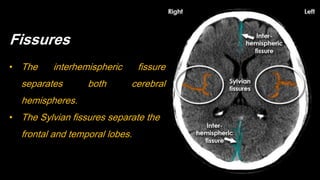

Fissures

• The interhemispheric fissure

separates both cerebral

hemispheres.

• The Sylvian fissures separate the

frontal and temporal lobes.